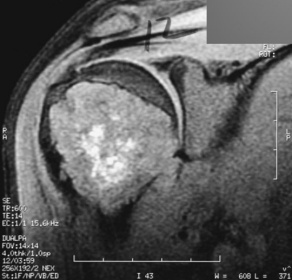

Chondroblastoma